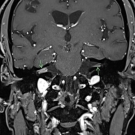

Catherine Anderson-Quinones, BM; Kinza Khan, BA; Sonal Khedkar, BS ; Andrew Wilner, MD; Jay Patel, DPM, MD

The patient was a 48-year-old man who presented with headache, left eye ptosis, a dilated pupil, and tooth pain for 10 days duration. They had a history of hypertension and poorly controlled type 2...

A 67-year-old man who developed new onset neurological symptoms was found to have bilateral internal carotid artery (ICA) pseudoaneurysms on computed tomography angiography.